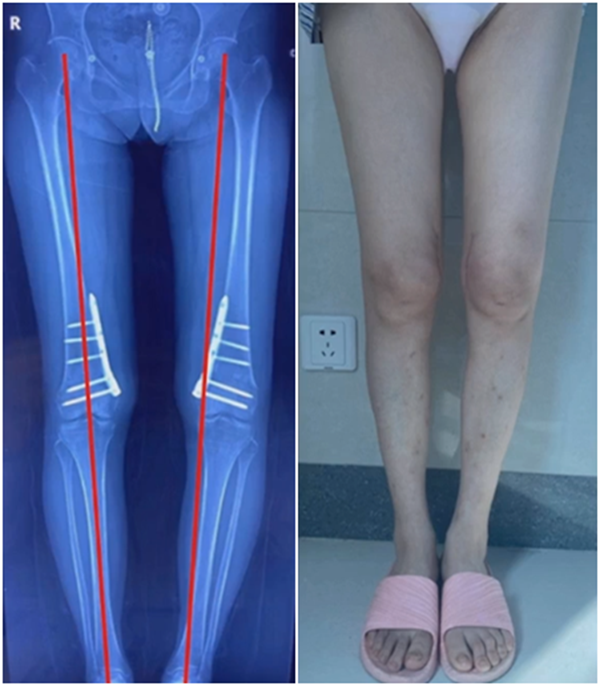

病例,X患者,女,双侧外翻膝,行双侧DFO。

术后6周摔伤,一侧出现膝内翻。

影像学检查显示左侧出现合页断裂。

进行翻修,术前力线显示内翻。